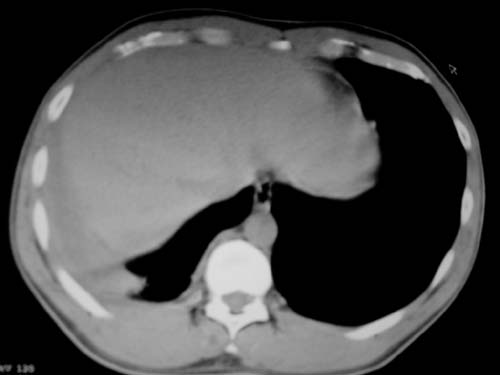

标题: CT19540: 31岁。自述结核性胸水治疗两个月后,在外院拍x线发 [打印本页]

标题: CT19540: 31岁。自述结核性胸水治疗两个月后,在外院拍x线发

右侧胸壁结节状软组织影伴相应肺叶内受侵,伴右侧胸腔积液。考虑:结核性可能大。

支持 右侧胸壁结节状软组织影伴相应肺叶内受侵,伴右侧胸腔积液。考虑:结核性可能大。

右侧胸壁结节状软组织影伴相应肺叶内受侵,伴右侧胸腔积液,结合临床,首先考虑结核。

1)考虑右侧结核性胸膜结节。2)右侧胸膜增厚+包裹性胸腔积液。